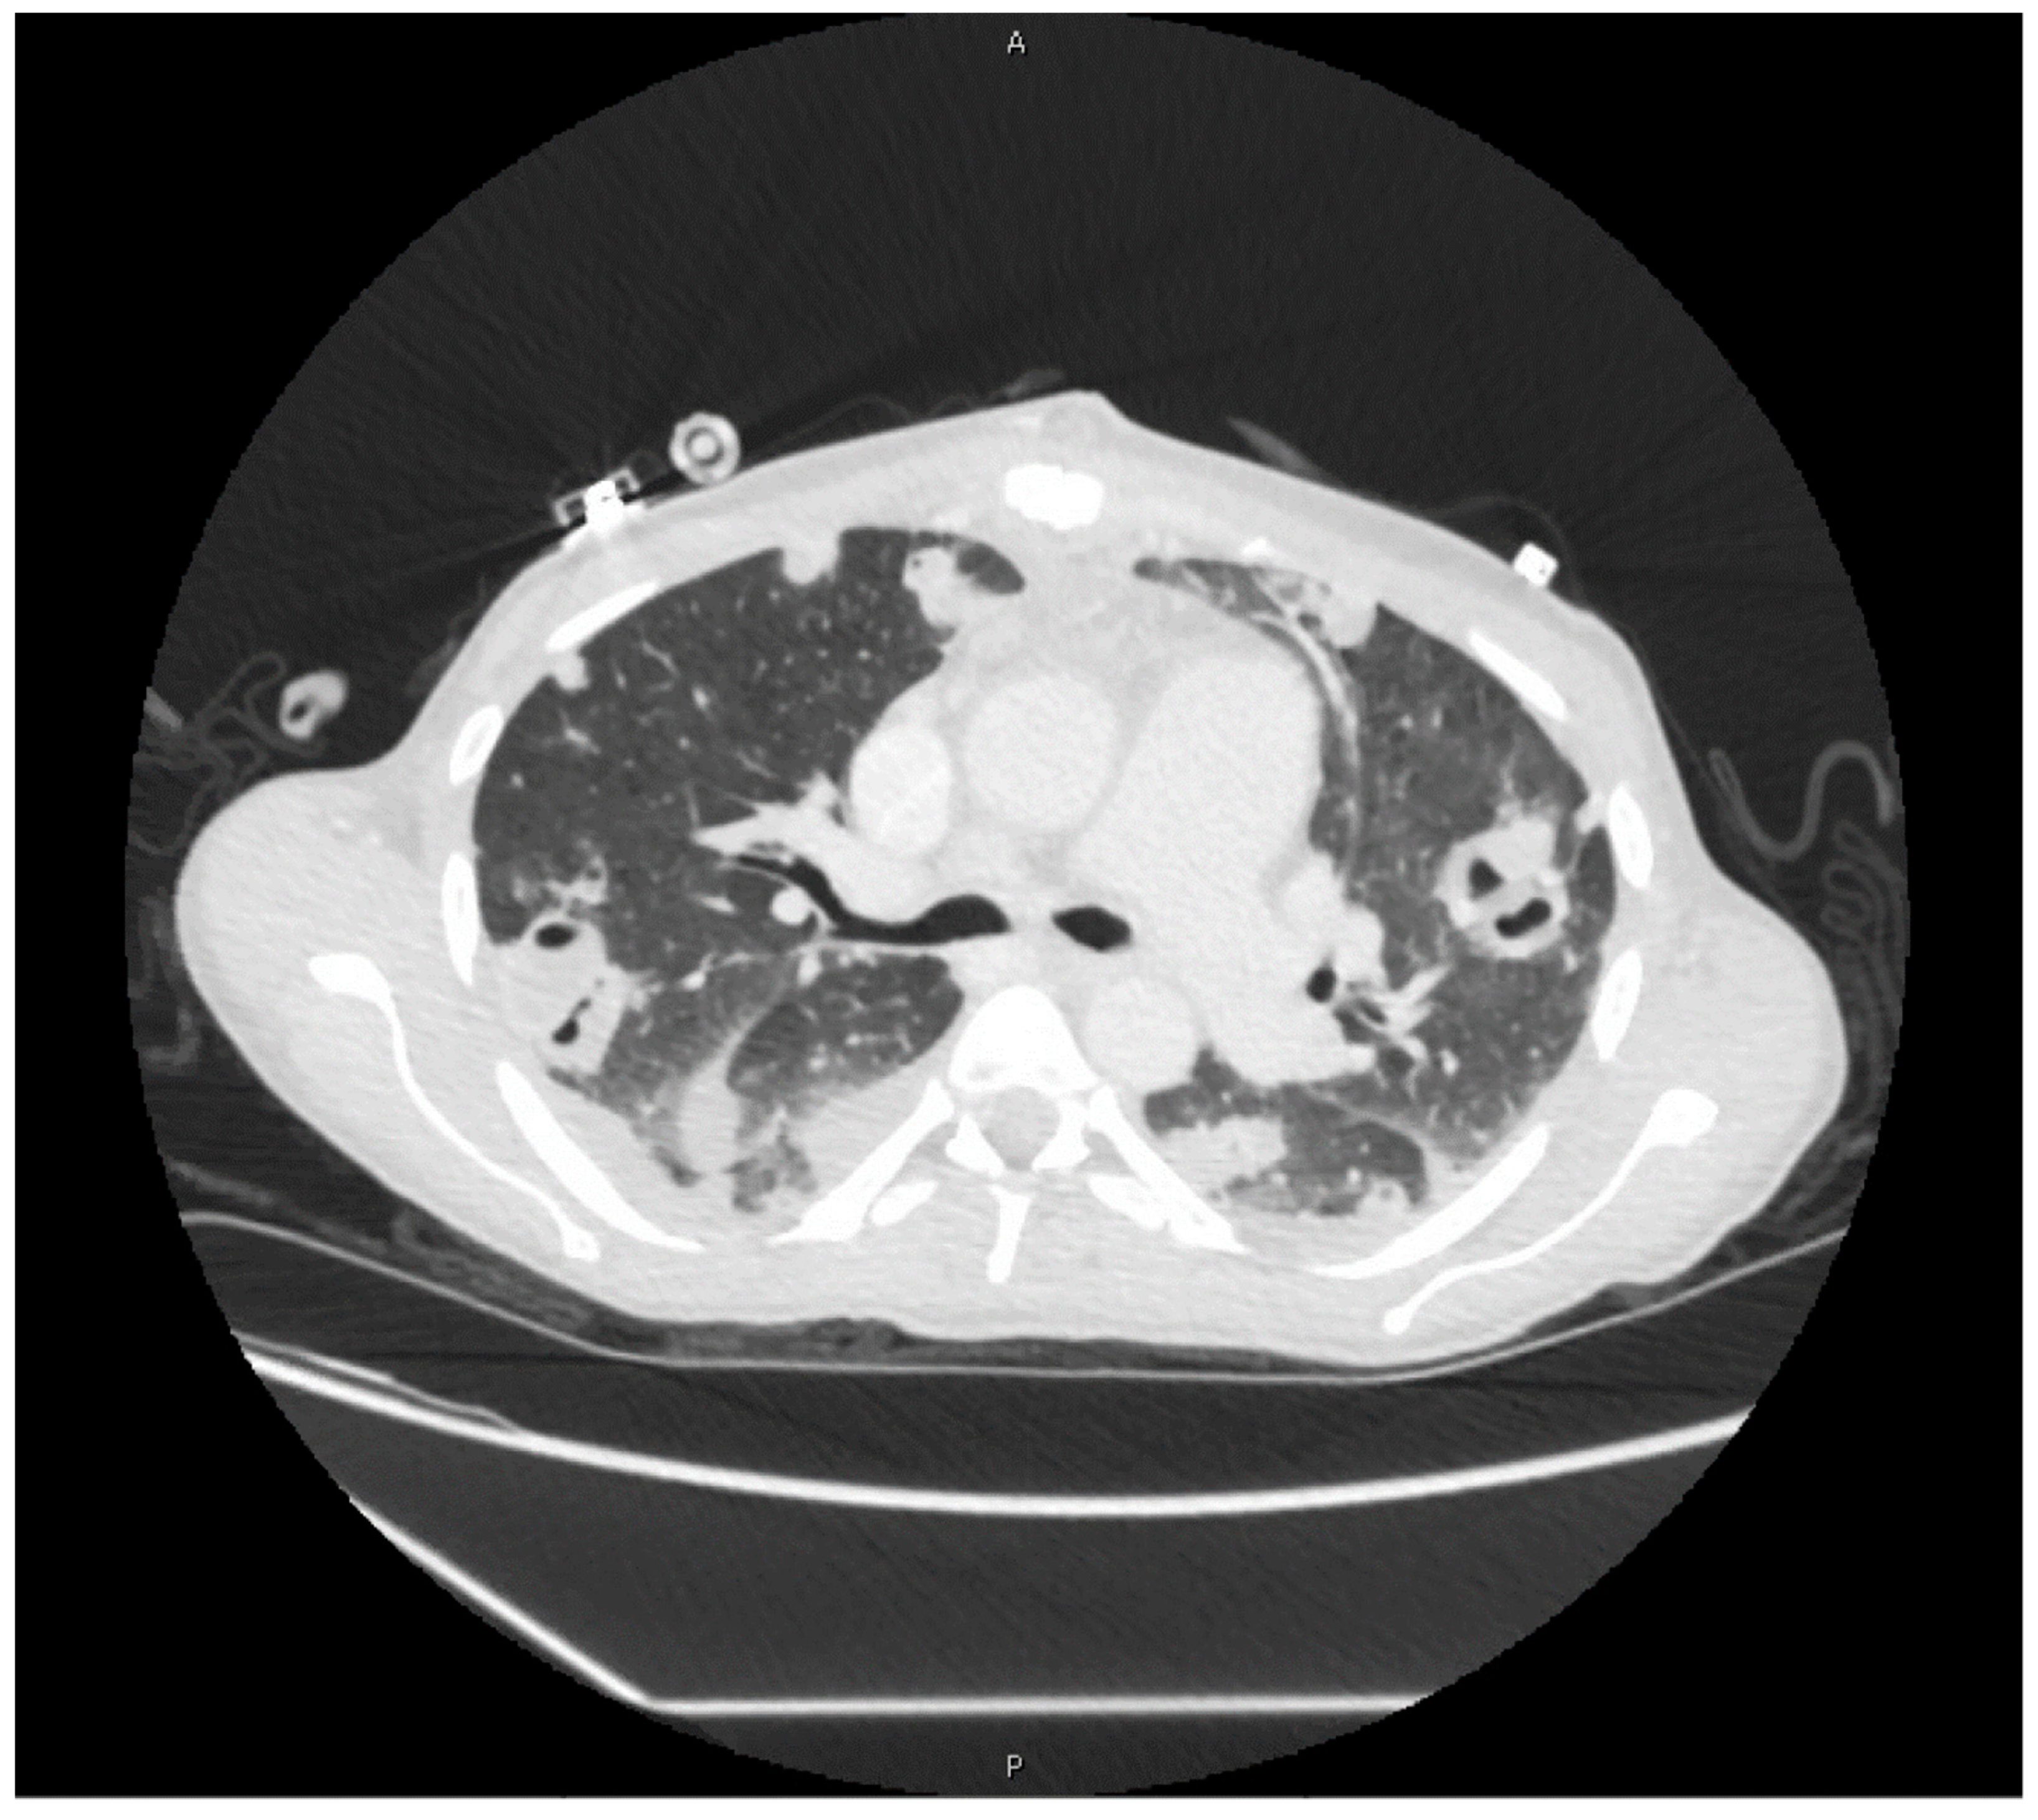

2. Case Presentation